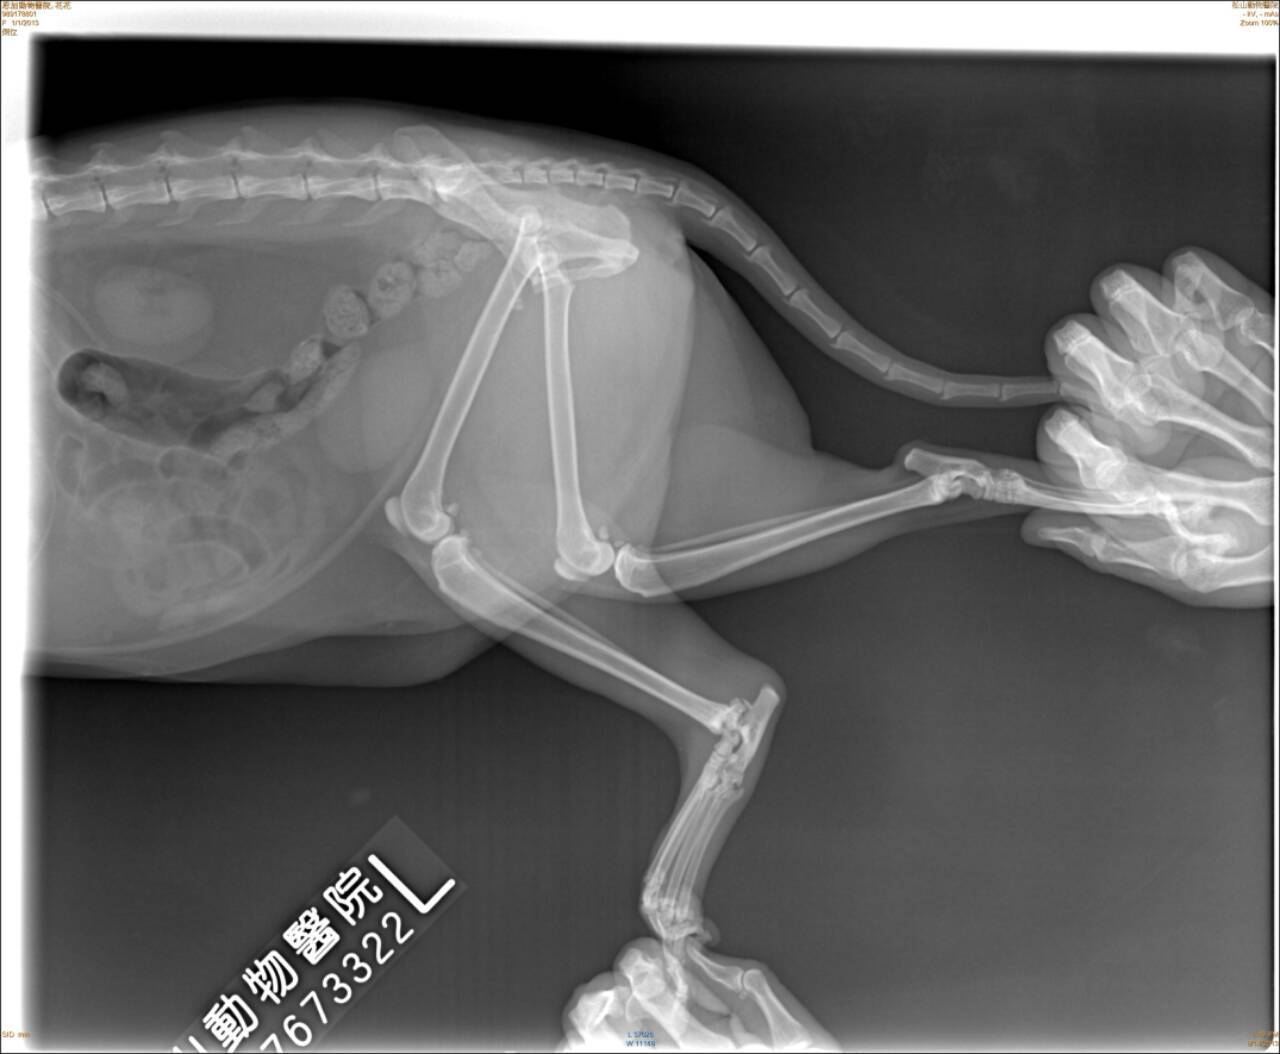

趕緊送往配合醫院~恩加動物醫院檢查。經觸診及照X光片,醫生表示花花的左後肢腳跟關節粉碎性骨折、脫水、白血球上升到三萬多。

經與醫師討論請教,醫師建議不宜動刀、因為粉碎性骨折無法接合只能打板固定,但如此一來反而會讓腳僵直無法動彈。預計先施打點滴補充體力、抗生素、止痛針,等貓咪穩定後要讓貓自行活動進行腳的復健,但已不適合回到接頭流浪了。

8/14住院,照X光片。